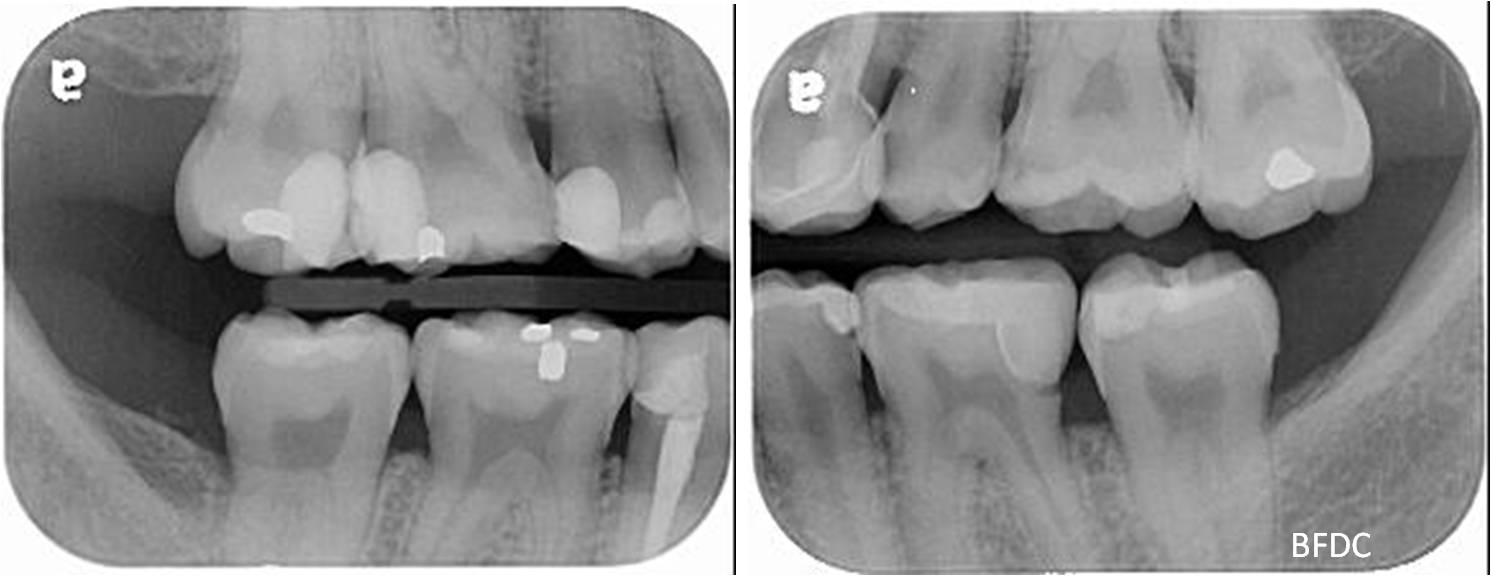

陶瓷崁體及冠蓋體-蛀牙-#1516172526 大範圍的補皮,該如何選擇,嵌體的方式就適用於大範圍的填補,因為它是一體成形, 嵌體材質多種,以往才會使用黃金合金,但因價格昂貴且顏色太過突出,因此現在多使用玻璃陶瓷二氧化鋯等材質的全瓷冠。嵌體有其優勢,因一體成形的材料,硬度和穩定性都較高,不用一點一點填補,減少下方凹陷重複蛀牙的危機,也不會變形或染色,美觀度高很多。 #1516172526蛀牙 #1516172526蛀牙 崁體及冠蓋體修形 安裝模型至咬合器 嵌體及冠塊體製作 陶瓷崁體及冠蓋體 黏著後 黏著後X光 術前、術後比較 嵌體有其優勢,因一體成形的材料,硬度和穩定性都較高,不用一點一點填補,減少下方凹陷重複蛀牙的危機,也不會變形或染色,美觀度高很多。

能避免片狀樹脂造成的,下方重複蛀牙,或彈性大造成咬合不舒服的問題,若有多顆牙齒填補,或坑陷較大者,如牙齒已蛀超過1/2或2/3者,才建議使用此種方式。